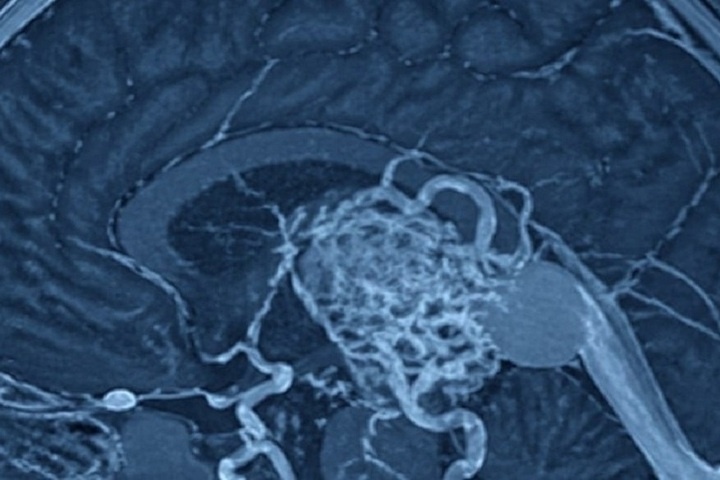

Нижегородского младенца, которому исполнилось всего три дня, удалось спасти благодаря мастерству врачей из Санкт-Петербурга. У новорожденного была выявлена серьёзная врождённая аномалия головного мозга. Ему поставили диагноз: артериовенозная мальформация вены Галена. Без своевременного хирургического вмешательства шансы на выживание были крайне малы, поскольку сердечно-сосудистая система не справлялась с перегрузкой, а кровеносные сосуды мозга подвергались повышенному риску разрыва. По распоряжению главного неонатолога Министерства здравоохранения РФ, ректора Санкт-Петербургского государственного педиатрического медицинского университета Дмитрия Иванова, младенца срочно доставили в Северную столицу. 26 апреля провели успешную эндоваскулярную операцию, которая спасла жизнь новорождённому пациенту.